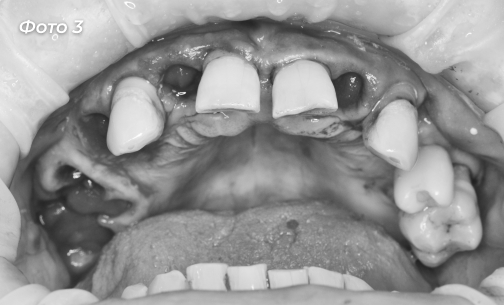

Пациенту были удалены некоторые зубы на верхней челюсти, остальные оставлены под опору для временного протеза (Фото 3, 4).